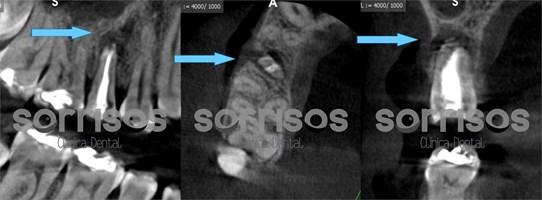

Se realiza un CBCT de la zona y se observa gran lesión con pérdida de la cortical ósea vestibular: